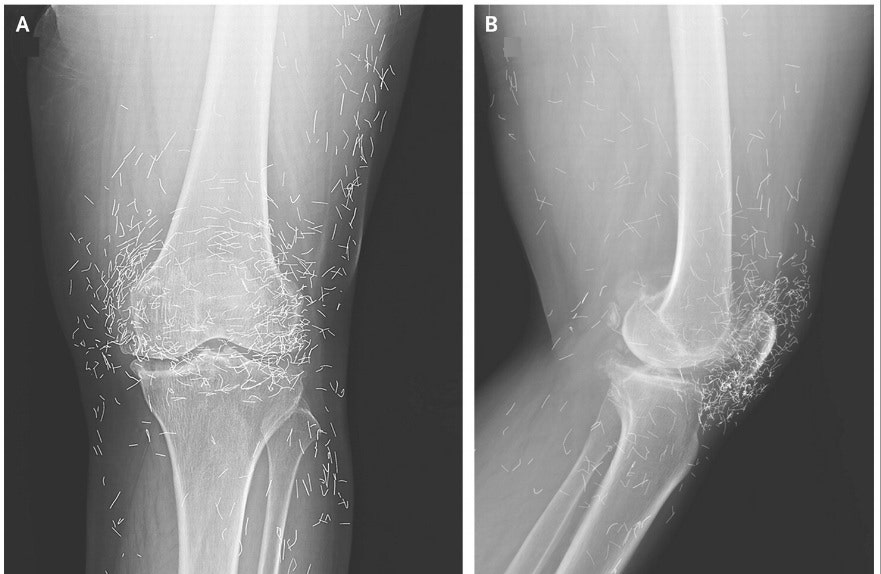

XRay Reveals Hundreds Of Gold Acupuncture Needles In Woman's Knees Knee Pain Cured By Acupuncture Acupuncture is one of the first lines of defense now recommended against chronic pain, especially in the knee. This review has found evidence that acupuncture that meets specified criteria for adequacy is superior to sham (or placebo). Is there a difference in the effectiveness. Its overall effect size is 0.8, and it can be considered instead of non. We want. Knee Pain Cured By Acupuncture.